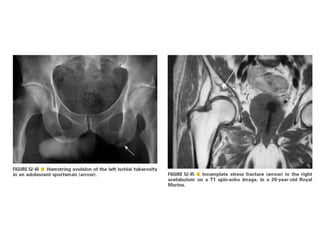

Skeletal trauma was presented by Dr Laith Fadhel with reference to Grainger's Diagnostic Radiology textbook. The presentation covered skeletal trauma as assessed through diagnostic radiology techniques. Key findings and treatments for skeletal injuries were likely discussed.